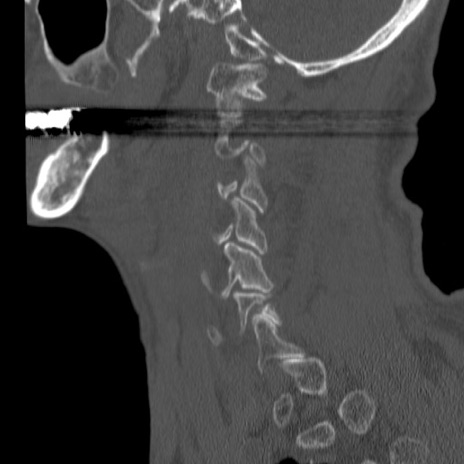

症例46 頚椎CT(矢状断像)

【症例】80歳代男性

【主訴】両側頚部〜上肢のしびれ

【現病歴】昨日、自宅内で転倒、その後より上記症状あり。意識障害なし。

【身体所見】両側上肢のallodynia(熱痛覚過敏)あり。MMTおよびDTRは正確な所見取れず。両上肢の挙上はなんとか可能。

異常所見と診断は?